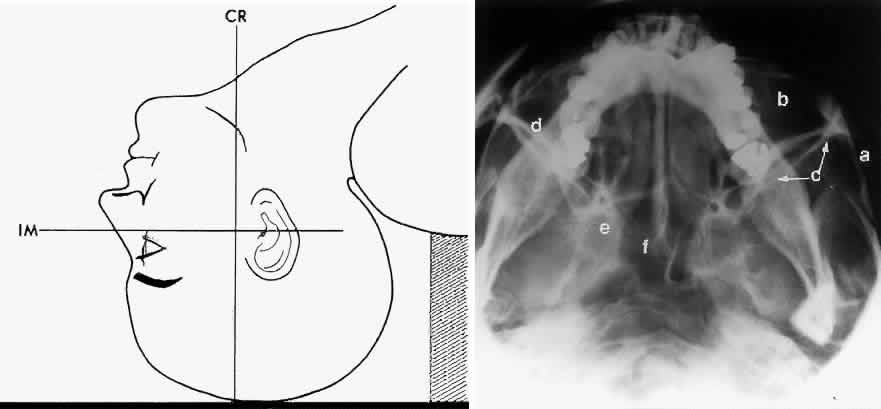

BASAL PROJECTION (SUBMENTO-VERTEX)

The basal projection (Fig. 5) for the evaluation of the sphenoid sinus and skull base was described initially by Arthur Schuller12 in 1905 and later popularized in this country by Bowen.13 This projection is obtained with the patient's neck extended either in the supine or upright position. The top of the head is placed so that the infraorbitomeatal line is parallel with the x-ray cassette. The x-ray beam is directed at right angles to the infraorbitomeatal line.5,6 This view shows the lateral walls of the orbit and maxillary sinuses well. The nasopharynx, pterygoid plates, pterygopalatine fossa, and the sphenoid and ethmoid sinuses may also be inspected. Because of the extreme head position, any history of a neck injury is a contraindication to this radiologic study.

Fig. 5. A. Schematic showing positioning for a basal projection. (CR, central ray; IM, infraorbitomeatal line) B. Radiograph of a basal projection. (a, zygomatic arch; b, orbit; c, lateral orbital wall; d, posterior wall of maxillary sinus; e, pterygoid plate; f, sphenoid sinus) (A; Rao VM, Gonzalez CF: Plain film radiography and polytomography of the orbit. In Gonzalez CF, Becker MH, Flanagan JC [eds]: Diagnostic Imaging in Ophthalmology, pp 1–7. New York, Springer Verlag, 1986)